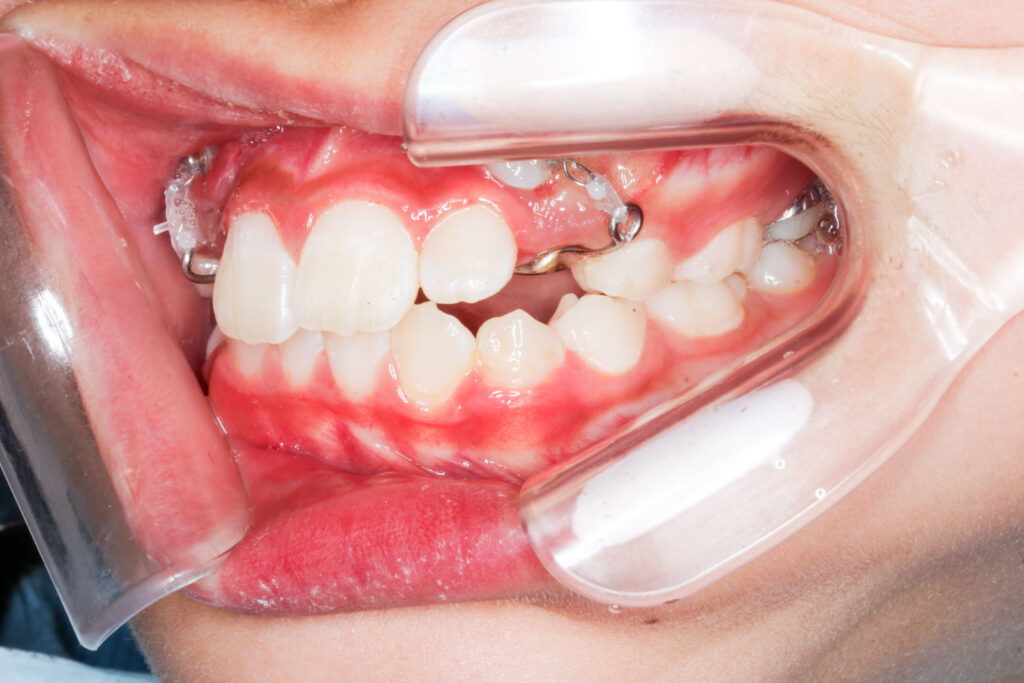

Before

年齢 10代

治療装置 上は裏側の矯正装置(フルリンガル)

治療内容 非抜歯

治療期間 2年8か月

リスク 歯の移動に伴う痛み、歯肉退縮、歯根吸収、歯肉炎、虫歯

主訴 ガタガタと隙間が気になる

症状 叢生と正中離開

治療回数 36回程度

総額費用 140万円程度